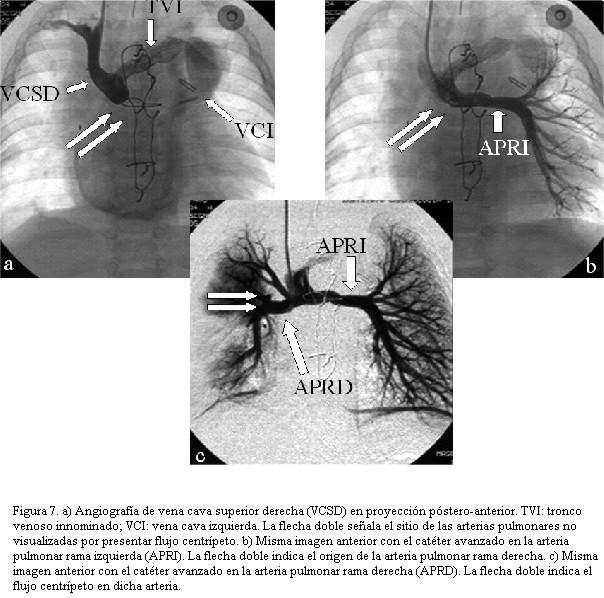

A los cuatro meses derivación cavopulmonar bidireccional (Glenn), y posterior embolización de colaterales aortopulmonares con coils (figuras 7, 8, 9 y 10).

Al segundo paciente se le otorgó el alta con saturación de 85%, el seguimiento mostró a los 2 meses hipoxemia marcada, comprobándose estenosis proximal y distal en las uniones tubo – ventrículo derecho y tubo – arterias pulmonares, efectuándose angioplastia con catéter balón de las mismas, posteriormente se realiza la cirugía de derivación cavopulmonar bidireccional con buena evolución inicial. A los seis meses de edad presenta marcada y progresiva caída de la saturación, siendo reestudiado identificando gran cantidad de colaterales desde la aorta hacia la arteria pulmonar rama derecha con flujo centrípeto por la misma las cuales son embolizadas con coils, quedando con flujo cavopulmonar centrífugo y saturaciones por encima del 85%, buena función del ventrículo único y recuperación ponderal.